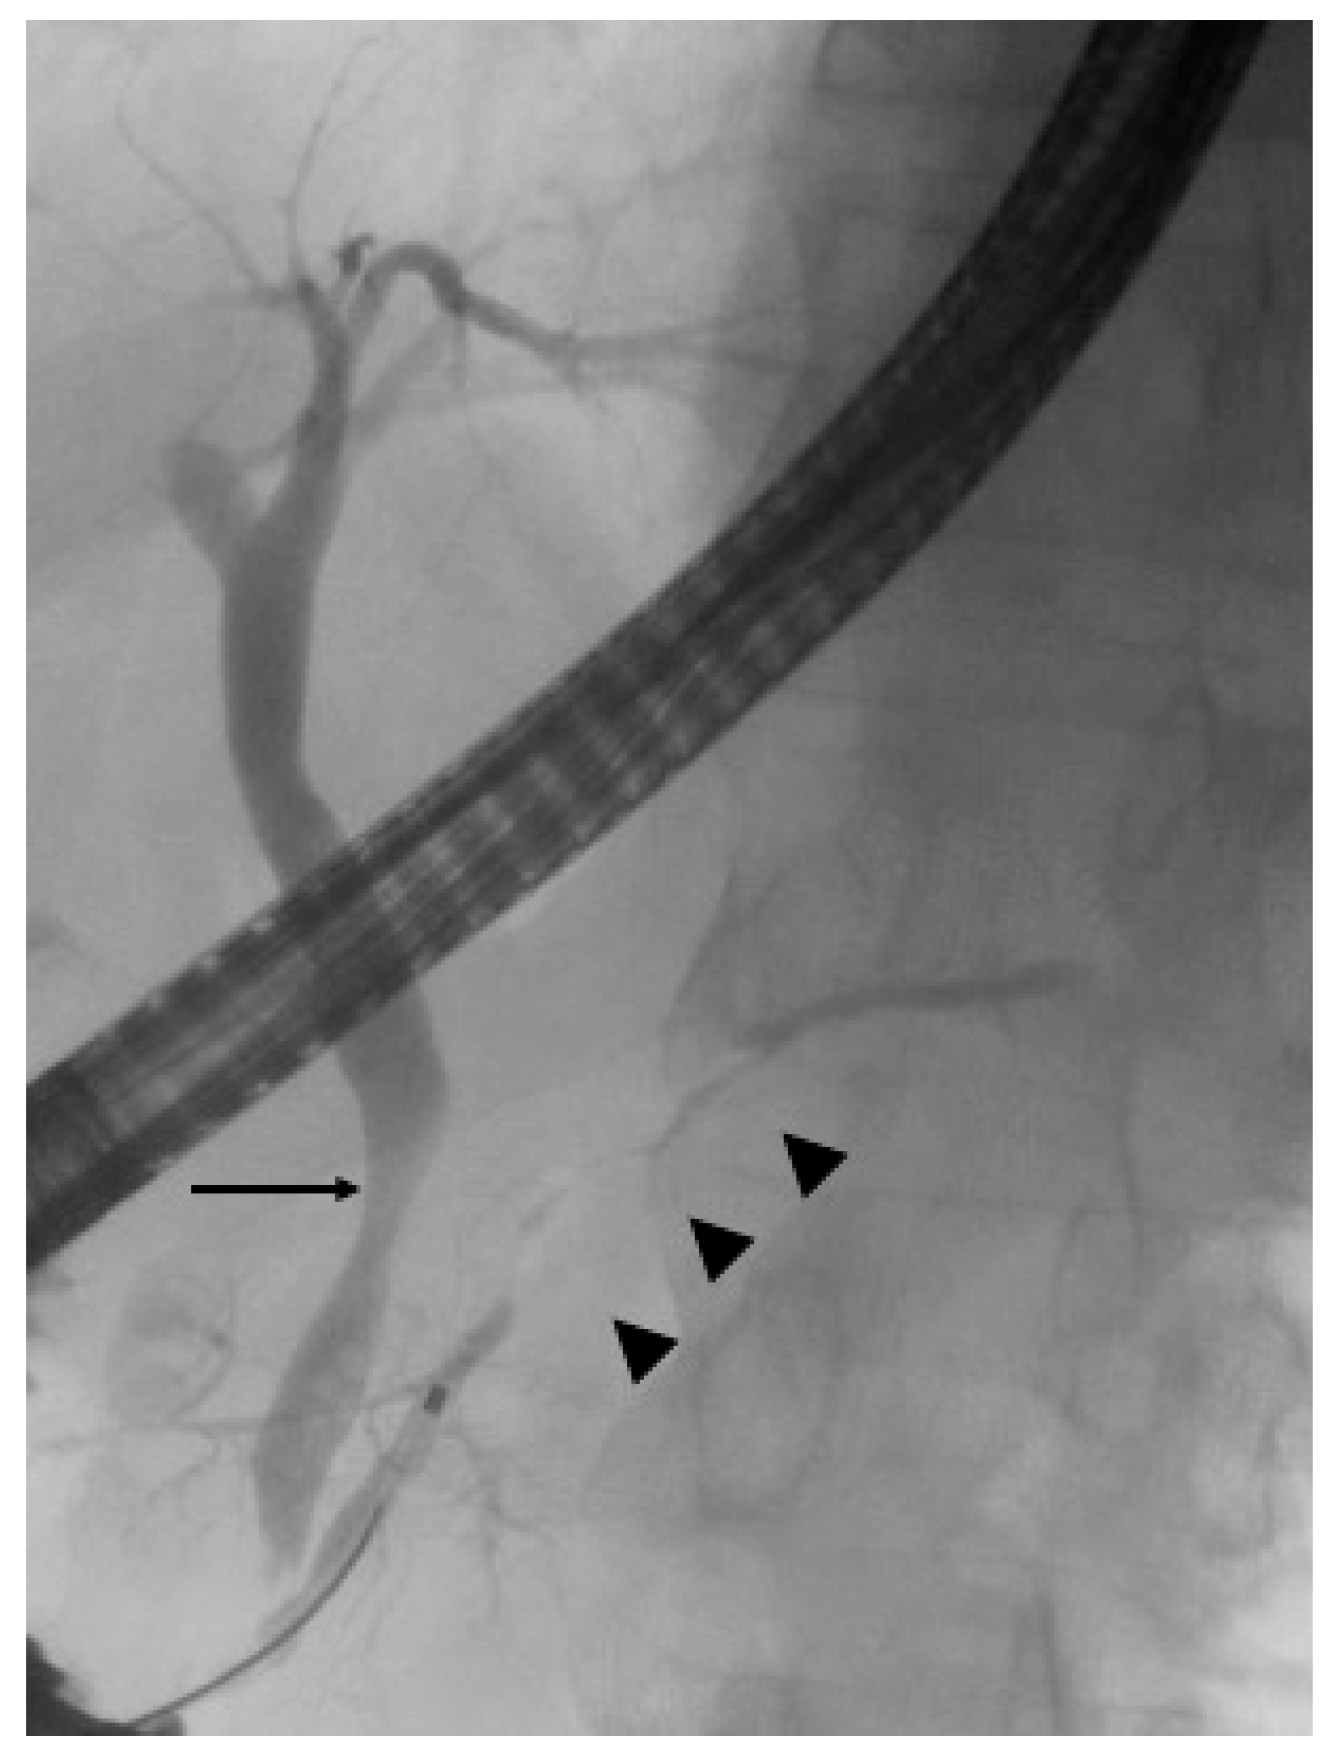

3.1. Endoscopic Retrograde Cholangiopancreatography

- Nakazawa, T.; Ohara, H.; Sano, H.; Ando, T.; Joh, T. Schematic classification of sclerosing cholangitis with autoimmune pancreatitis by cholangiography. Pancreas 2006, 32, 229. [Google Scholar] [CrossRef]

- Nakazawa, T.; Ohara, H.; Sano, H.; Aoki, S.; Kobayashi, S.; Okamoto, T.; Imai, H.; Nomura, T.; Joh, T.; Itoh, M. Cholangiography can discriminate sclerosing cholangitis with autoimmune pancreatitis from primary sclerosing cholangitis. Gastrointest. Endosc. 2004, 60, 937–944. [Google Scholar] [CrossRef]